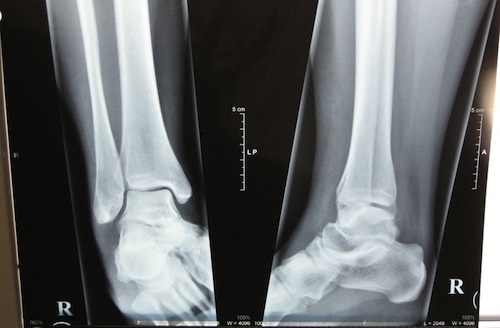

Me ha devuelto las radiografías de mi tobillo derecho, y como no me ha visto muy convencida de que el dolor se me pase, pues me ha recetado más sesiones de fisioterapia, de nuevo bajo mi criterio personal (estudiar medicina y luego dejar la decisión en manos de los pacientes… ains).